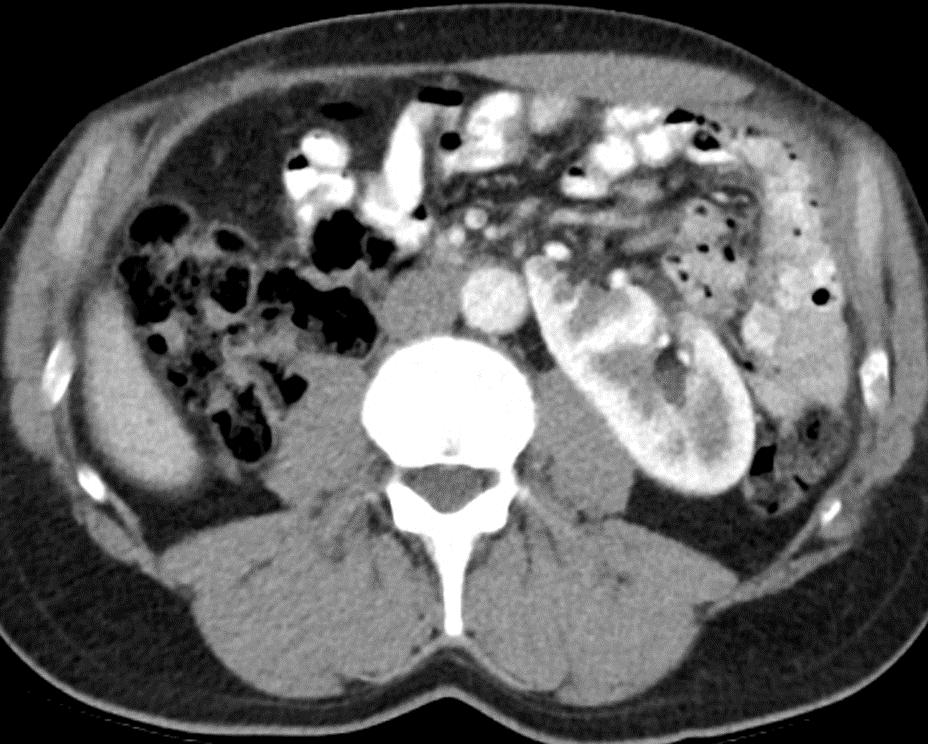

Obr. 1. Perioperační CT snímek během MWA.

Fig. 1. Perioperative CT scan during microwave ablation.

Výkon byl prováděn mikrovlnným systémem Solero Microwave Tissue Ablation System (AngioDynamics, Inc., USA). Během ablačních výkonů byla používána frekvence 2,45 GHz a výkon v rozsahu 100–140 W. Jako aplikátor byla používána nerezová ocelová jehla s keramickým hrotem o průměru 15 G a délce 14, 19 nebo 29 cm. Jedna ablační sekvence po zavedení jehly do tumoru trvá 4–6 min podle velikosti nádoru, v průběhu jednoho výkonu jsou standardně prováděny 1–2 ablační sekvence. Maximální velikost ablační zóny udávaná výrobcem je 54 × 39 mm na jednu sekvenci. Po skončení ablace tumoru se během vytahování jehly provádí ablace-koagulace punkčního kanálu (track ablace). Výkon je prováděn v analgosedaci za přítomnosti anesteziologa, pacienti snášejí výkon dobře. Celková doba výkonu vč. polohování pacienta a přípravy CT pracoviště je 60–90 min (obr. 1).